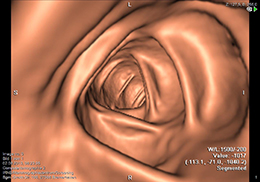

CT Colonographie – Tut das weh?

Bei der CT-Colonographie (Virtuelle Koloskopie) handelt es sich um eine gering invasive radiologische Methode zur Darstellung des Dickdarmes (Colon). Hierfür ist eine mehrtägige Vorbereitung und die Entleerung des Darmes erforderlich. Letztere erfolgt in gleicher Weise wie für eine konventionelle Darmspiegelung (Coloskopie), deren Details Ihnen von unserer Anmeldung mitgeteilt werden. Da die CT-Colonographie im wesentlichen wie eine normale Abdomen-CT abläuft, sind die notwendigen Laborbestimmungen dieselben. Wie für diese ist auch die Injektion eines jodhaltigen Kontrastmittels erforderlich (siehe auch den Abschnitt Computertomographie).

Bei der CT-Colonographie werden keine Schmerz- oder Beruhigungsmittel verabeicht. Allerdings erfolgt häufig eine intravenöse Injektion von Butylscopolamin (Buscopan®), um den Darm zu entspannen, was die Sehfähigkeit und die Fahrtüchtigkeit einschränken kann. Bitte planen Sie dies und eventuell eine Begleitung für den Nachhauseweg ein.

Zu Beginn der Untersuchung wird ein dünner Katheter in den Enddarm eingeführt, über den Luft in den Darm eingeleitet wird, um ihn zu erweitern. Dies ist für eine optimale Beurteilung des Darmes erforderlich. Ein dadurch entstehendes kurzzeitiges Druckgefühl ist völlig normal. Danach erfolgt eine intravenöse Injektion von jodhaltigem Kontrastmittel und ein erster Scan des gesamten Abdomen in Rückenlage des Patienten. Anschliessend wird in Bauchlage, falls erforderlich, weitere Luft in den Dickdarm eingebracht, und ein zweiter Scan mit reduzierter Strahlendosis durchgeführt.

Die Befundung der erstellten Aufnahmen erfolgt an Hochleistungsrechnern durch unsere Radiologen mit Hilfe spezieller Programme nicht nur im Hinblick auf den Dickdarm, sondern für das gesamte Abdomen.